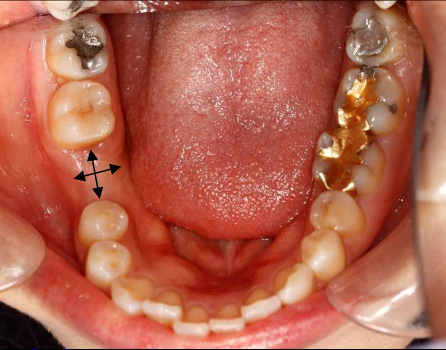

What are components of a site specific clinical evaluation?

Mesial-Distal space

Buccal-lingual alveolar ridge width

Condition/anatomy of teeth adjacent to the site

Health of mucosa

Site specific occlusion-super eruption/ vertical clearance

A dental implant requires about 1- 2mm of bone around the entire implant body

How much horizontal space is needed?

Minimum space between tooth and implant: 1.5 mm

Avoid damaging PDL, preserve proper blood supply

Minimum space between implant and implant: 3 mm

Adequate space to allow for soft tissue “cuff”/papilla formation

Buccal/lingual bone layer at least 1 mm thick

Tooth dimensions and recommended implant diameter

What are some considerations regarding the width of ridge?